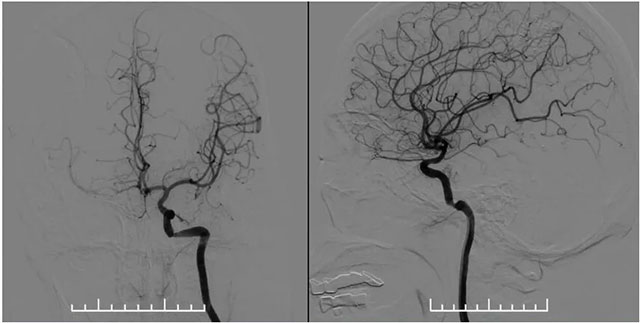

▲ 左側(cè)頸內(nèi)動脈造影見巖骨段遠端狹窄,右側(cè)大腦中動脈由左側(cè)頸內(nèi)部分代償

MR示雙側(cè)基底節(jié)區(qū)及右側(cè)頂葉凸面小梗塞(部分軟化灶形成)輕度腦白質(zhì)疏松,MR-tof 可見左側(cè)頸內(nèi)動脈巖骨段狹窄。DSA血管造影:左側(cè)椎動脈支架內(nèi)再狹窄,左側(cè)頸內(nèi)動脈造影見巖骨段遠端狹窄,右側(cè)大腦中動脈由左側(cè)頸內(nèi)部分代償,右側(cè)頸動脈造影提示右側(cè)頸內(nèi)動脈閉塞。